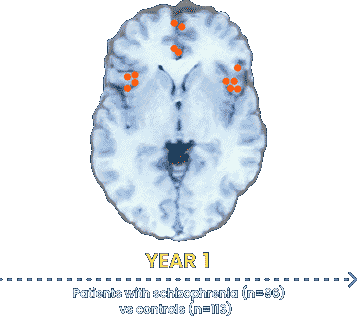

Differences between groups were superimposed on a model MRI image.

Orange circles indicate areas of decreased gray matter density in the frontal and temporal lobes of patients with schizophrenia.

More recent data are emerging that continue to explore the relationships between schizophrenia and cortical matter changes.14